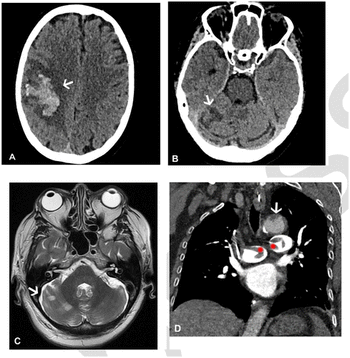

Greater imaging utilization has increased the prevalence of incidental findings or incidentalomas, but unclear clinical context and guidelines complicate management. Accordingly, these authors offer a thorough review of the literature and discuss new opportunities for improving interdisciplinary management strategies.